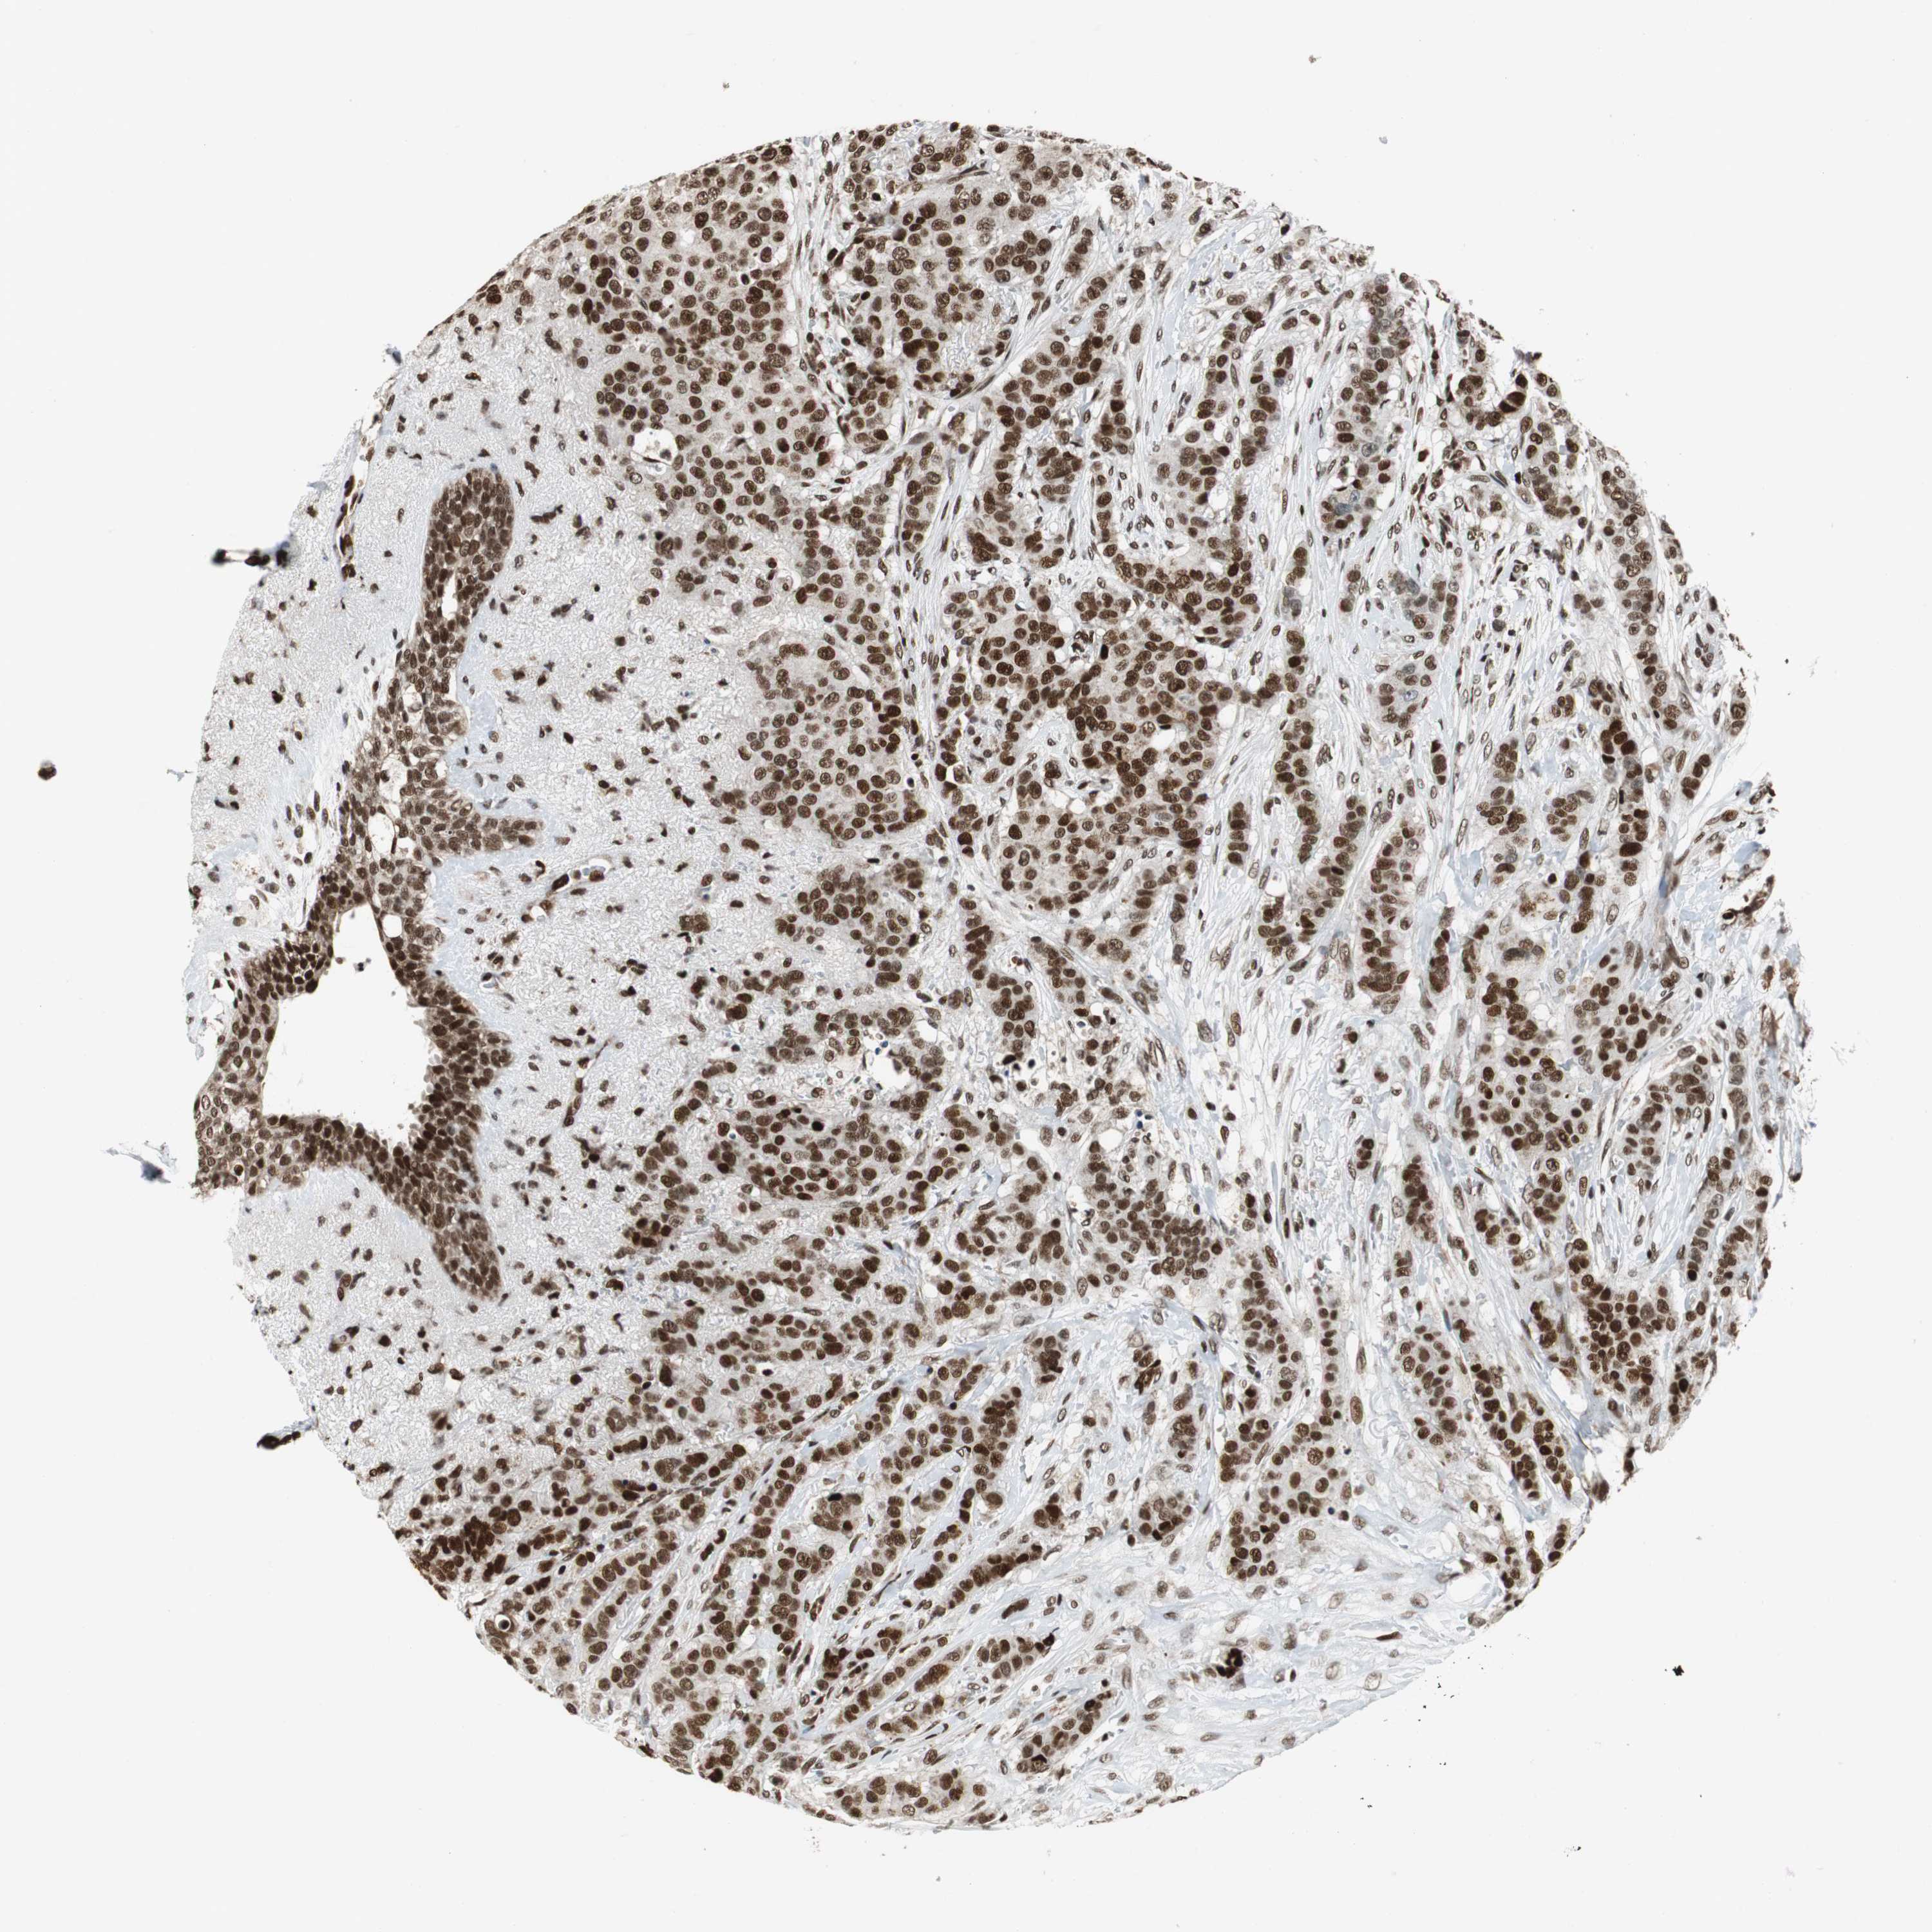

CANCER BREAST CANCER Show tissue menu

BRCA TCGA BRCA VALIDATION PROTEIN EXPRESSION